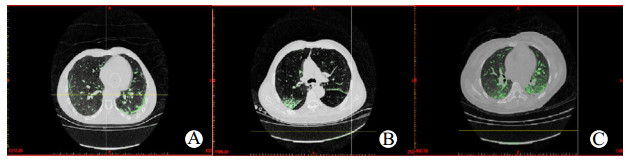

1.2.2 定量分析患者胸部HRCT患者胸部HRCT通过GE工作台(Advantage Workstation 4.4; GE Healthcare)由一名工作15年的放射科医生进行三维重建,该医生仅行三维重建,不能阅读临床资料。建模步骤可以分为4步:读取图像、提取轮廓、选择热区、生成三维模型。选择热区按照Oikonomou等[12]所采取的方案,本研究把肺内病变根据CT值分为四个部分:过度通气区(CT阈值:-1000HU到-901HU)、正常通气区(CT阈值:-900HU到-501HU)、通气减低区(CT阈值:-500HU到-101HU)和不通气区(CT阈值:-100HU到100HU)。在本研究中主要观察肺磨玻璃影改变对急性PQ中毒患者预后的影响,而磨玻璃影改变可以近似看作为通气减低区域。入组患者在入院第3、5、7天行肺HRCT检查,调取患者原始影像资料,导入工作台行三维重建。选择CT阈值-500HU至-101HU为磨玻璃影改变热区,标记热区颜色为绿色,通过蒙版编辑把肺外相同CT值的其他组织部分剪掉(图 1~2)。同样的方法标记过度通气区、正常通气区和不通气区,并蒙版编辑肺外区域后,计算四个区域的总和即肺的容积,最后计算磨玻璃样体积占肺的体积比(V%GGOs)来量化分析磨玻璃影。

| A~C分别代表第3、5、7天;绿色为所选热区(CT值-500 HU至-101 HU) 图 2 死亡组同一病例第3、5、7天GGOs改变 Fig 2 Changes of GGOs on the 3rd, 5th and 7th day in the same person of the death group |